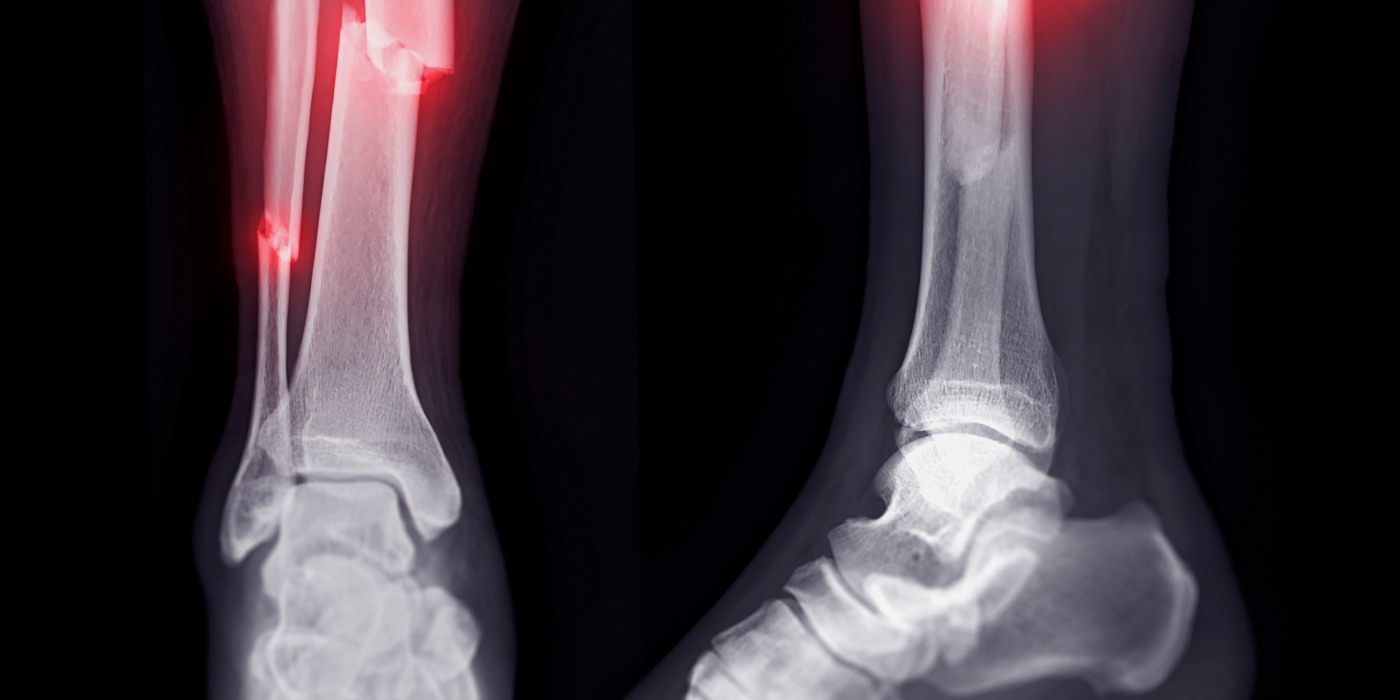

골절 후 방치 시간이 길어질수록 뼈가 잘 붙지 않고,

혈액 공급이 차단되어 뼈 조직이 괴사할 위험이 커집니다

특히, 골절 후 72시간(3일 이내)가 치료 성패를 가르는 골든타임입니다.

• 01. 골절 내원 즉시 진단

• 02. 최신형 3d 기반 골절 진단 및 수술 planning

• 03. 환자, 상황별 상이한 골절 기전에 따른

정확한 수술 계획